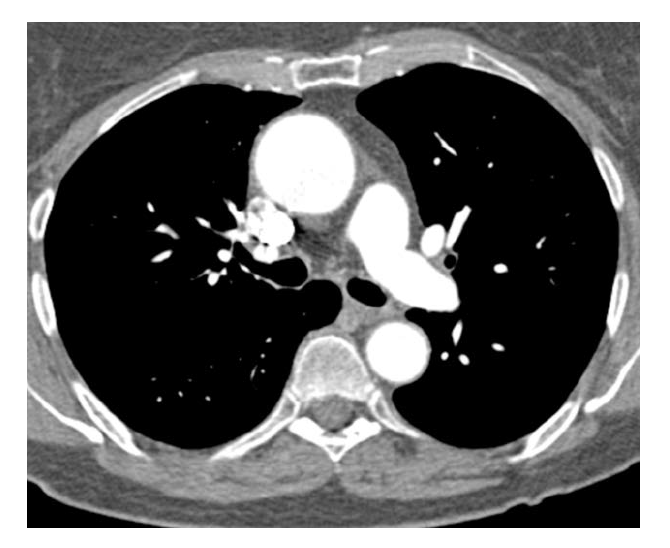

What is this?

Aortic dissection